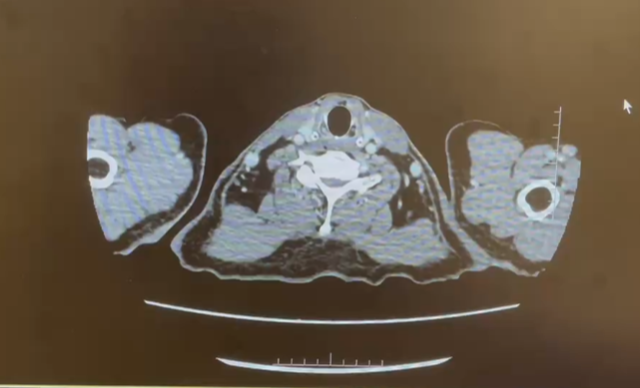

CT平扫+增强

检查诊断:

1.下腔静脉管腔较前缩小、充盈缺损较前略减少;

2.右肾静脉栓子同前;左肾静脉充盈缺损未见显示;双侧骼静脉充盈欠佳;

3.右肾上极病变同前:恶性肿瘤可能;右肾盂管壁增厚强化:受累?

4.盆腔少量积液;

5.右肝动脉起自肠系膜上动脉;左下肺动脉栓子;

日期:2024.3.3